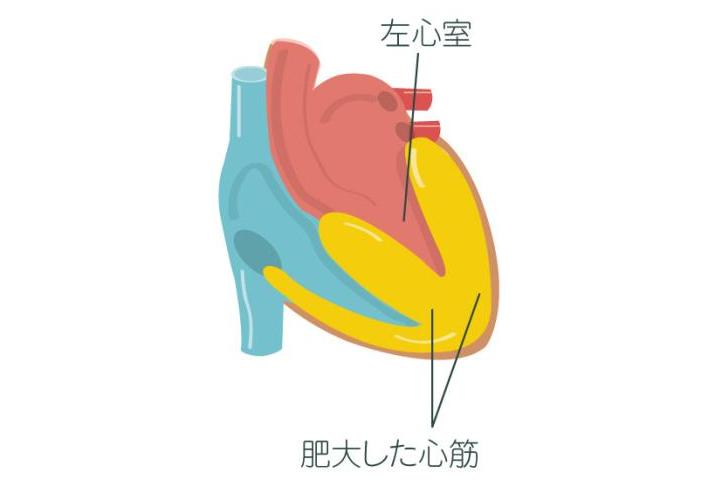

コロナ後遺症に多い心筋炎・心膜炎に要注意!2024.06.27

コロナ後遺症に多い心筋炎・心膜炎に要注意!2024.06.27 -